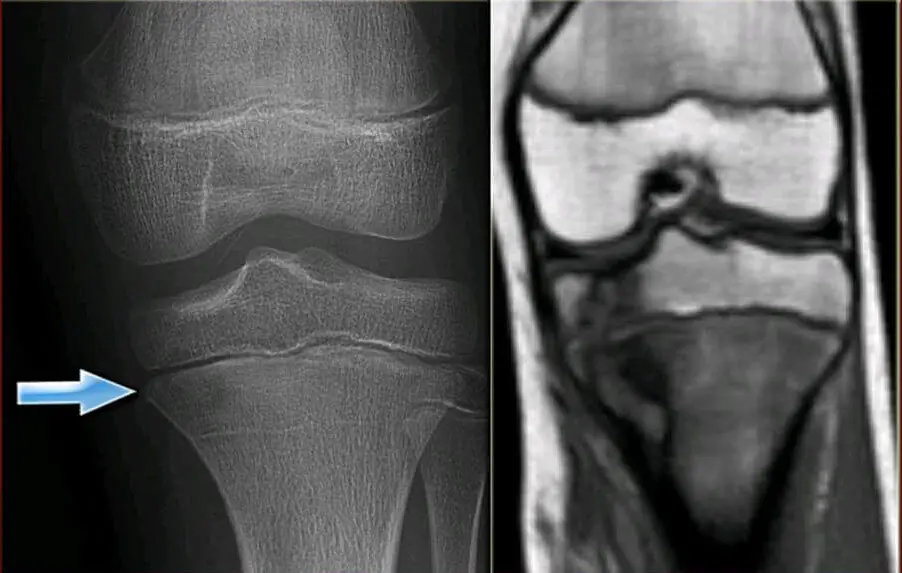

МРТ коліна дозволяє бачити тонкощі і особливості ушкодження тканини коліна, наприклад при травмі (меніски, зв’язки, скриті переломи кісток і багато іншого).

МРТ колінного суглоба (фото 1)

МРТ суглобів, читати більше.

Кожний метод дослідження не виключає проведення іншого. Наприклад, при артрозі немає можливості встановити точний діагноз тільки по МРТ. Потрібен ще і рентген.

Точно з’ясувати стадію артрозу коліна можна тільки за допомогою рентгену.